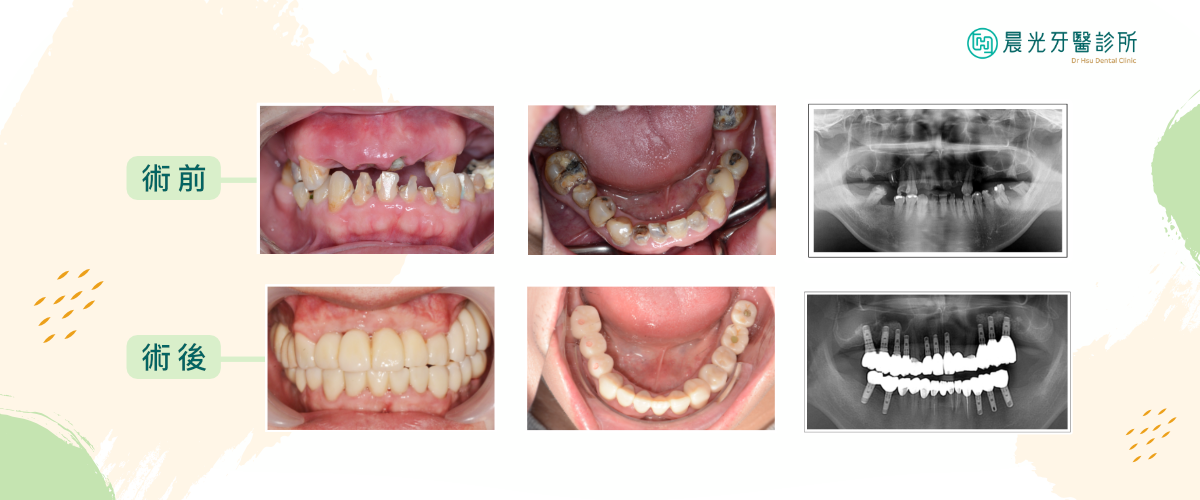

因此全⼝重建的⾸要任務為牙周病的治療,治療後經過評估與討論,再將無法保留的牙⿒以植牙進⾏全⼝重建。恢復全⼝的⿒列平衡,重建咬合關係。

術前根據患者狀況進⾏軟硬組織重建,待有⾜夠組織量後,將植體植入⿒槽骨,待植體與骨組織完整密合後再將假牙固定在植體上。

⼈⼯植牙已是成熟的治療技術,可藉由舒眠植牙、微創植牙或植體導航等⽅式,讓病患在舒適、迅速、傷⼝⼩的狀態下,安全安⼼的接受治療。植牙的穩定程度與咬合能⼒都與真牙相仿,並且不需將鄰近的牙⿒磨⼩或拔除,患者可以擁有與真牙相同的完整咀嚼能⼒,⾃由享受美食。